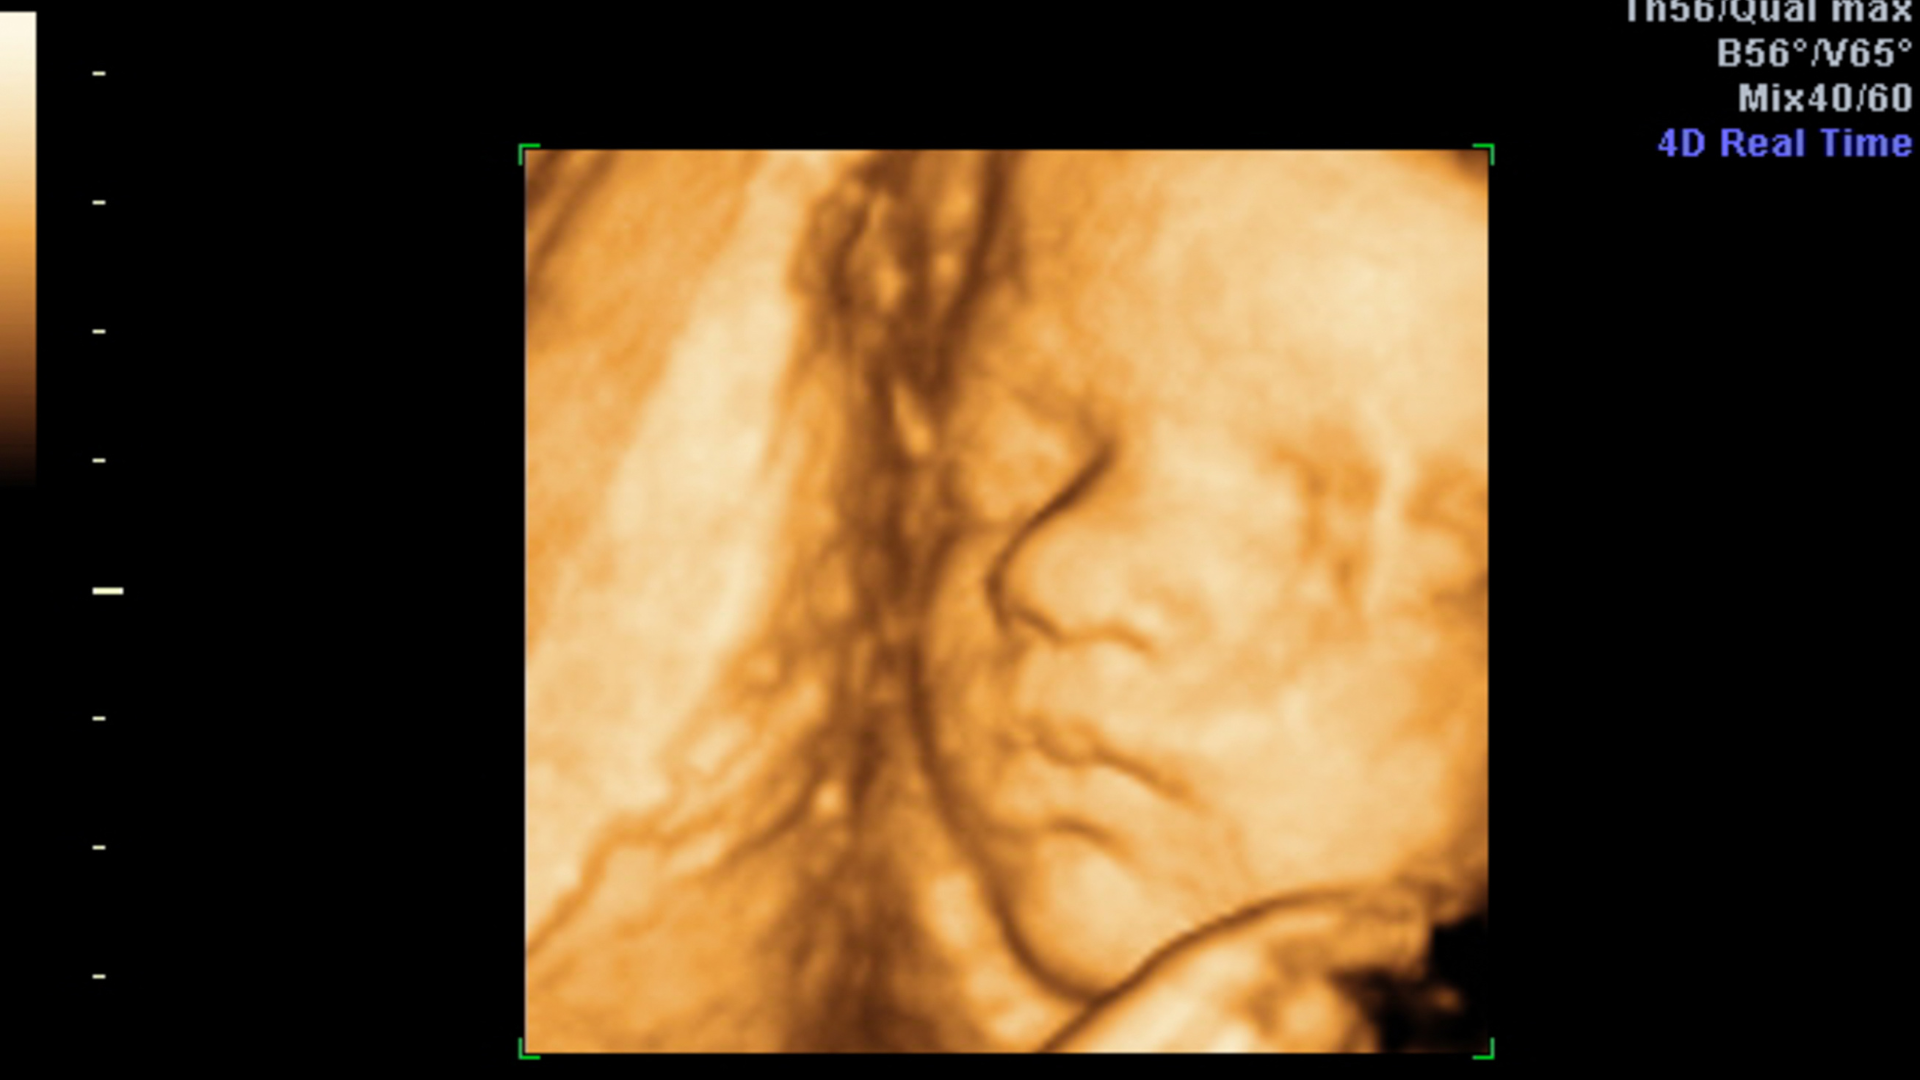

3D Ultraschall